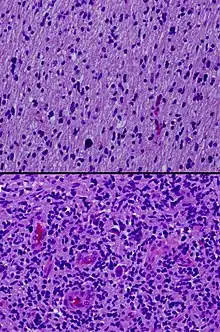

In pathology, grading is a measure of the cell appearance in tumors and other neoplasms. Some pathology grading systems apply only to malignant neoplasms (cancer); others apply also to benign neoplasms. The neoplastic grading is a measure of cell anaplasia (reversion of differentiation) in the sampled tumor and is based on the resemblance of the tumor to the tissue of origin.[1] Grading in cancer is distinguished from staging, which is a measure of the extent to which the cancer has spread.

Pathology grading systems classify the microscopic cell appearance abnormality and deviations in their rate of growth with the goal of predicting developments at tissue level (see also the 4 major histological changes in dysplasia).

Cancer is a disorder of cell life cycle alteration that leads (non-trivially) to excessive cell proliferation rates, typically longer cell lifespans and poor differentiation. The grade score (numerical: G1 up to G4) increases with the lack of cellular differentiation - it reflects how much the tumor cells differ from the cells of the normal tissue they have originated from (see 'Categories' below). Tumors may be graded on four-tier, three-tier, or two-tier scales, depending on the institution and the tumor type.